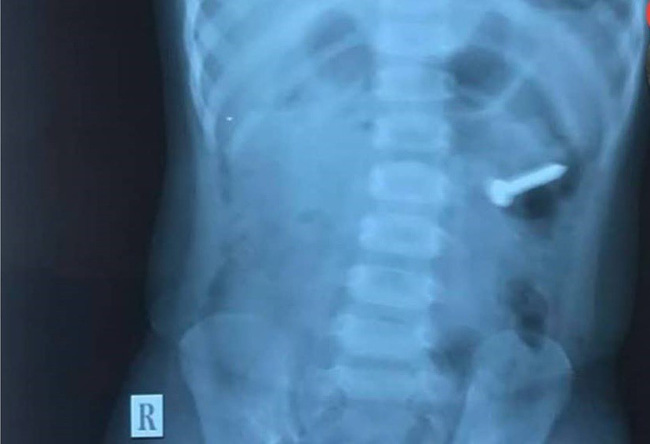

Hình ảnh phim chụp X-quang khiến chị Hòa tá hỏa.

Chị Hòa thấy bé lớn đang thò tay móc miệng bé út mới vội vàng chạy ra. Chị gọi chồng vào, kể lại sự việc. Bố bé mới sực nhớ ra là con trai lớn cầm đinh không biết vứt đi đâu, tìm mãi không thấy. Chị Hòa hoảng hốt đưa con đi viện, chụp X-quang và tá hỏa với kết quả khi nhìn thấy hình ảnh chiếc đinh trong bụng của con.